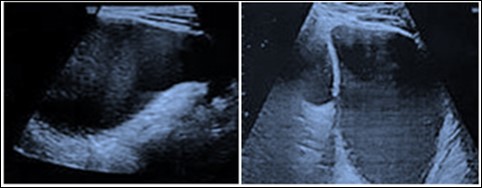

34 year old G2P1001 was referred to our institute at 21weeks period of gestation for a fetal abdominal cystic mass for further evaluation and management. At referral, she had an anomaly scan reporting a left sided retroperitoneal collection of 3x2 centimeters with septations surrounding the kidney and extending up to left pelvis suggestive of lymphocoele in the fetus. In second trimester anomaly scan nuchal fold thickness was normal, there were no markers suggestive of aneuploidy and no other malformation was seen. In follow-up scans, there was increase in size of the collection upto 8x6 cm at term which also shown a subcutaneous component of around 5x4 cm along the left fetal torso in the lumbar region (Figure 2a). Growth parameters were normal and amniotic fluid was adequate. She was hypothyroid on treatment and developed gestational diabetes at 32weeks period of gestation which was managed with medical nutrition therapy. Her first child was born by cesarean section and had no congenital malformation. Index pregnancy was terminated by an elective cesarean section at term as she was not willing for vaginal birth after caesarean. Male baby of 3.4kg was born with good apgar score. He had a left sided lumbar cystic swelling of 5x6cm, reducible inguinal hernia and undescended testes on the left side. Postnatal echocardiography was normal and postnatal USG shown similar features of the cyst. Baby was active, euthermic, euglycemic, passed urine and stool and was well accepting feeds hence discharged at day 3 of life. He was conservatively followed and at 6 months postnatal visit, size of the lumbar swelling was clinically decreased in size and infant had age appropriate milestones. Ultrasonography (Figure 2b) and CECT scan at one year of age was suggestive of large cystic lesion in the abdomen and pelvis (13*6*12 cm) with extension into postero lateral subcutaneous planes of abdominal wall through a defect in the left oblique muscle. Rest of the abdominal organs and large vessels were normal and there was no ascites or lymphadenopathy. However child is doing well at one year of age without any clinical obvious increase in the size of lumbar swelling.